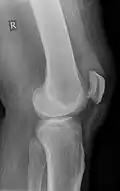

| An x-ray demonstrating quadriceps tendon rupture. Note the abnormal angle of the patella and soft-tissue swelling marked by the arrow. | |